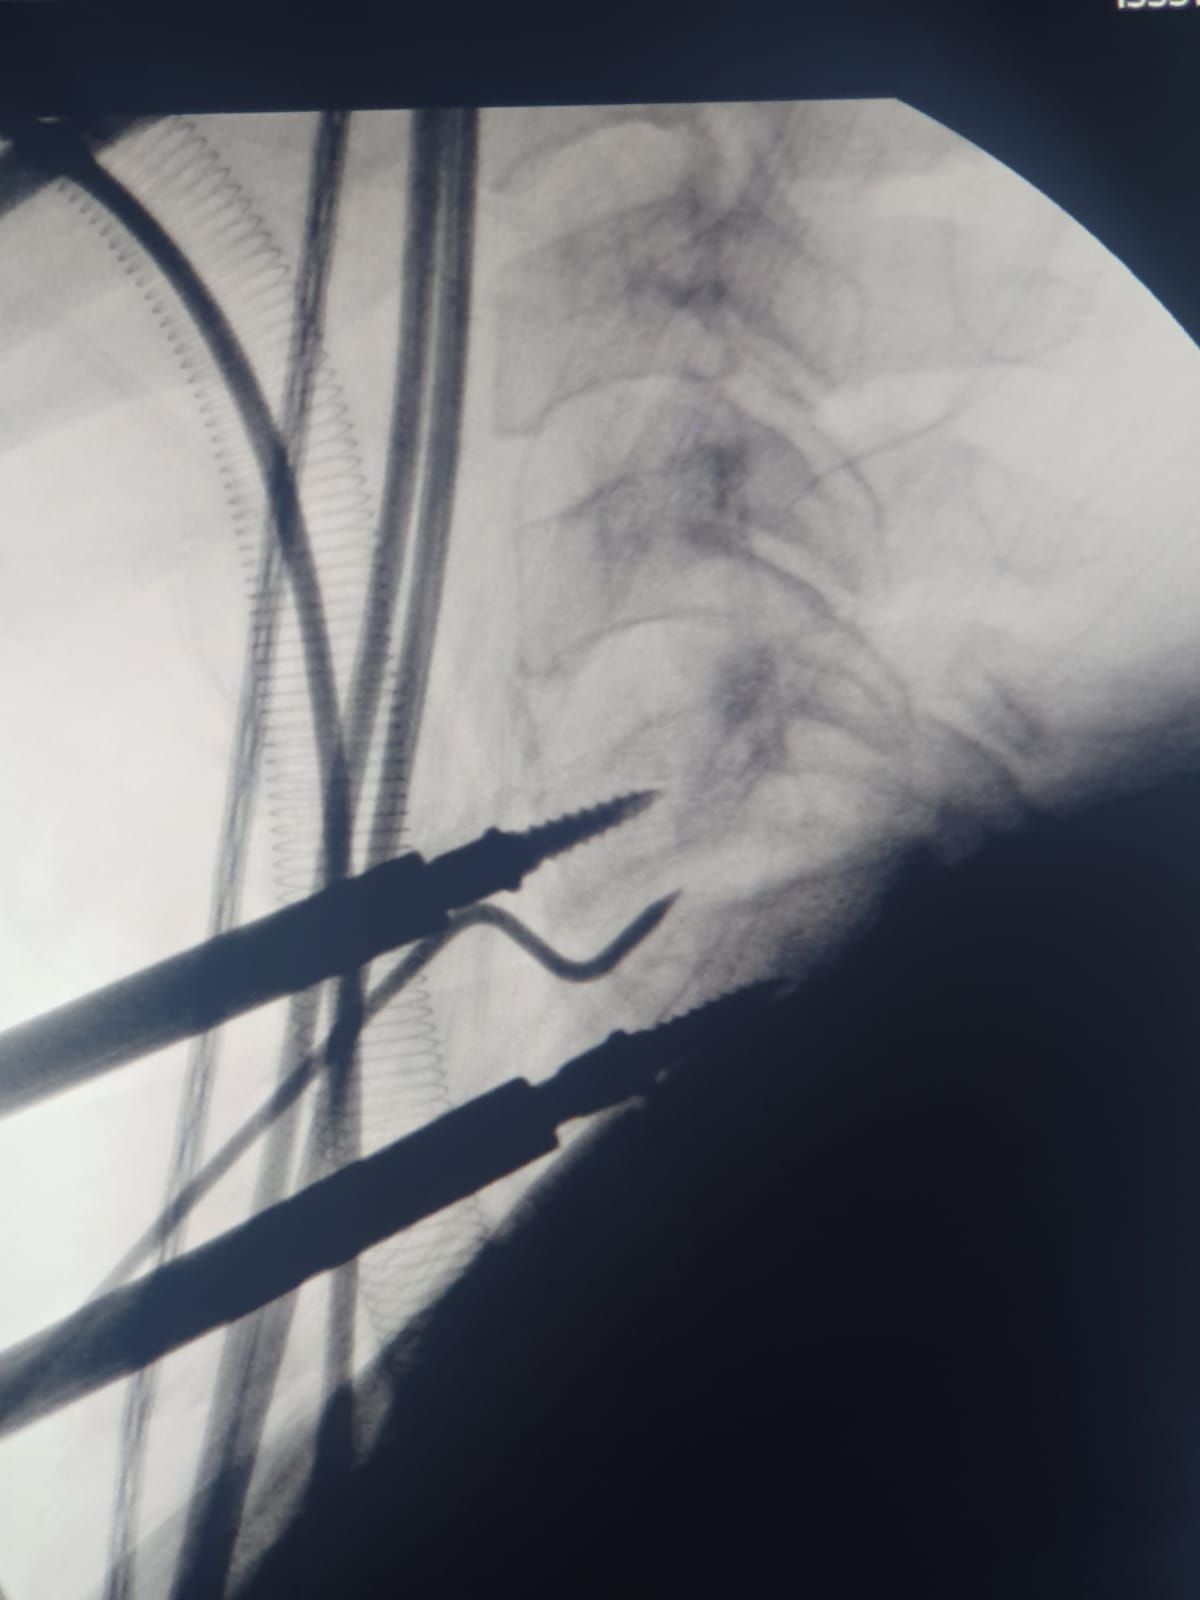

- Cirugía de Columna

- Cirugía Mínima Invasiva de Columna

Sin especificarMicrocirugía de hernia de disco

Sin especificarArtrodesis cervical anterior